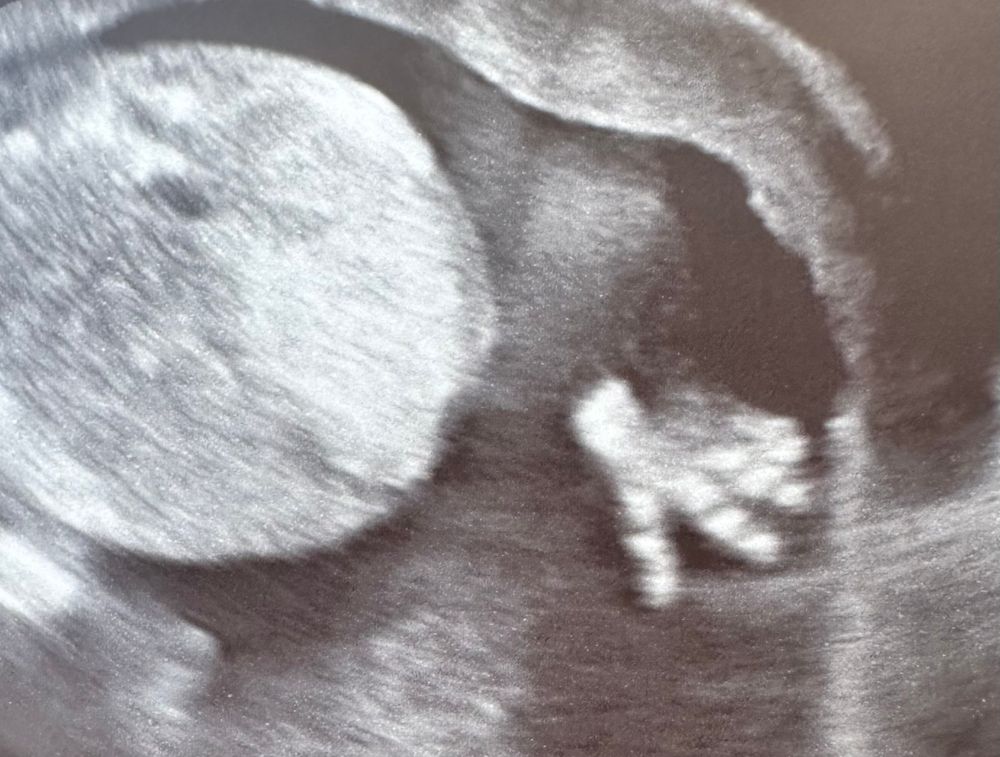

С наступающим 💕 В 15 недель уже не помещается на экран, да? ☺️ Милота)) Растите здоровенькими 🌺

07.03.2024

Ellie, Спасибо 😊 Это вид снизу)) Когда шейку мерили)